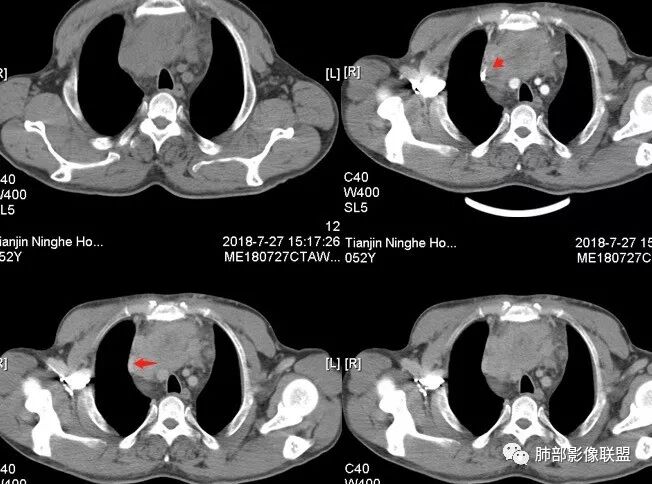

大雄:中年男性,发现左前胸壁血管曲张1天入院肿标:细胞角蛋白19片段明显增高,神经元特异性烯醇化酶稍高CT:前纵膈巨大实性占位,边缘膨隆,质地较硬,纵膈脂肪间隙模糊,压迫纵膈大血管(头臂静脉明显狭窄)但未见包绕。平扫可见囊变及钙化,增强中度延迟强化,可见大片不规则坏死区。未见纵隔淋巴结肿大,胸骨骨质破坏及胸水。考虑:恶性肿瘤,胸腺癌可能。

水晶石头 (许建林):患者中年男性,因左前胸壁血管曲张1天就诊。查体左颈前胸壁、左上臂静脉曲张。血管彩超左颈内血静脉流淤滞。肿标:细胞角蛋白19片段明显增高,神经元特异性烯醇化酶稍高胸部CT:前纵隔巨大实性占位,边缘膨隆、清晰,纵隔脂肪间隙模糊,压迫纵隔大血管,未见包绕。平扫可见囊变及钙化,增强中度延迟强化,可见大片不规则坏死区。未见纵隔淋巴结肿大、胸骨骨质破坏及胸水。综合考虑恶性肿瘤,胸腺癌可能性大,鉴别恶性畸胎瘤。

崔少钢:中年男性,左侧颈内静脉、左侧前胸壁及左上臂静脉曲张,提示有静脉阻塞,另患者有恶性家族史。影像:前纵隔占位,有浅分叶,周围脂肪间隙不清晰,且见小淋巴结,内有坏死,上腔静脉受侵,内有钙化,支持胸腺癌。

南边:边界大部分清楚,有些地方毛糙。

附近有淋巴结

上腔静脉如何?

心包如何?

大肿块,边缘不清,伴随肿大淋巴结,上腔静脉受侵犯——恶性